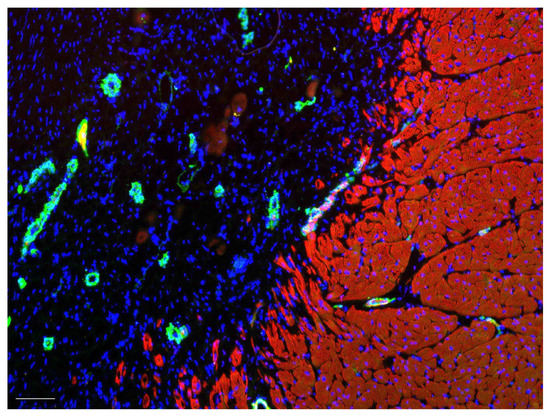

Figure 9.

Border zone between myocardium (stained with troponin T, red) and vascularized gastric patch (smooth muscle actin, green, all nuclei stained in DAPI (blue)). Immunohistochemistry. Bar indicates 100 µm.

From an immunohistological perspective, the myocardium remained clearly delineated from the implanted pericardium and stomach segment. Differentiation of the pericardium from the cicatricial tissue was immunohistochemically impossible. Overall, numerous cell nuclei could be stained in the graft tissue that epicardially bordered the myocardium six months after implantation. In all areas, there were capillaries and blood vessels.